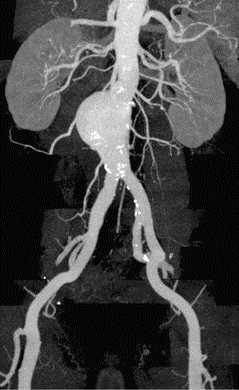

Помимо гипертрофии миокарда левого желудочка, склеротически измененных створок аортального клапана и наличия его недостаточности I степени, обращало на себя внимание расширение восходящего отдела аорты до 4,5-5,1 см (на различных уровнях) (рис. 1). Исследование средних отделов восходящей аорты (рис. 2) позволяло выявить нитевидную, невыраженно флотирующую структуру, расположенную по передней стенке аорты, формирующую истинный и ложный каналы аорты, которые более детально верифицировались в режиме ЦДК (рис. 3). В слепом участке ложного канала определялись тромботические массы. При исследовании из супрастернального доступа в области дистального отдела восходящей аорты и ее дуги лоцировался участок отслоения интимы (рис. 4). В остальных отделах аорты, доступных для визуализации, патологии выявлено не было. Таким образом, ультразвуковое исследование сердца позволило диагностировать расслаивающую аневризму восходящего отдела и дуги аорты (тип II по De Bakey). Проведенная МСКТ подтвердила данный диагноз (рис. 5).

Рис. 5. Мультиспиральная компьютерная томограмма больного Ж. Восходящий отдел и дуга аорты с визуализируемой отслоенной интимой.

Пациент в срочном порядке был направлен в кардиохирургический центр (г. Москва), где была выполнена операция: протезирование аортального клапана и восходящей аорты клапансодержащим кондуитом "Мединж" 25 мм по методике Bentall-DeBono в модификации Kouchoukos. Протезирование дуги аорты синтетическим протезом по модифицированной методике H. Borst с реплантацией брахиоцефального ствола и левой общей сонной артерии островковым методом и проксимализацией дистального анастомоза на уровне устья левой подключичной артерии (рис. 6).